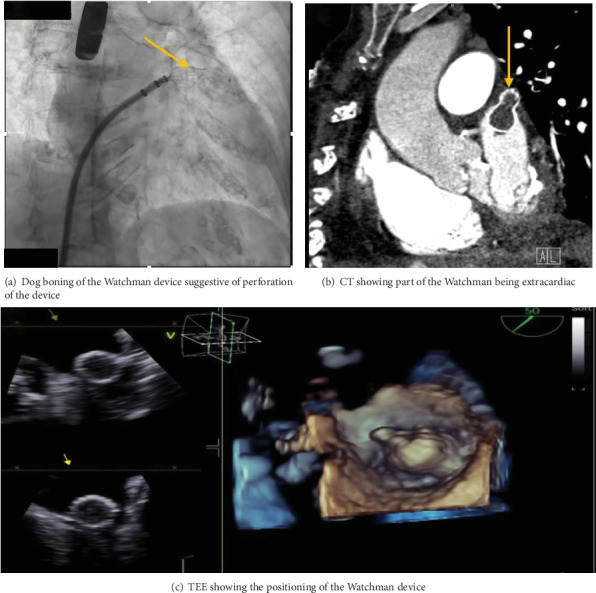

到2030年,美国将有超过1200万人患有心房颤动,这使中风的风险增加了五倍。Watchman装置是抗凝效果不佳的患者的一种选择。在此,我们报告一例罕见的左心耳(LAA)穿孔的Watchman装置植入病例,术中发现该装置部分位于心包间隙。一名93岁女性,有高跌倒风险,服用香豆素,接受瞭望者装置安置。植入过程中,发现LAA穿孔,部署过程中心包有收缩渗出,决定部署装置,希望它有助于密封泄漏。取出该装置被认为会使患者面临更大穿孔的风险。在此之后,成功的心包开窗术和临时引流术避免了胸骨切开,总体效果良好。一个自扩展框架覆盖左心房表面Watchman装置被部署,之后一个罕见的但潜在的并发症穿孔在分娩期间被注意到。留在原地的装置密封了泄漏,并防止了万一装置被取回时可能的恶化。最终,这个决定改善了病人的预后。

By 2030, the United States will have over 12 million people with atrial fibrillation, which carries a five-fold increase in risk of stroke. Watchman device is an alternative in patients who are poor candidates for anticoagulation. Here, we present a rare case of Watchman device implantation related to left atrial appendage (LAA) perforation noted intraoperatively with portion of the device in the pericardial space. A 93-year-old female with high fall risk and on Coumadin presented for Watchman device placement. During implantation, LAA perforation was noted with exudation of contract in the pericardium during deployment, and decision to deploy the device was made, hoping it would help seal the leak. Retrieving the device was thought to put the patient at risk of bigger perforation. Following which successful pericardial window with temporary drain placement avoided sternotomy and overall had a good outcome. A Watchman device with self-expanding frame covering the left atrial facing surface was deployed, after which a rare but potential complication of perforation was noted during delivery. The device left in place sealed the leak and prevented potential worsening incase device was retrieved. Eventually, this decision improved the outcome of the patient.